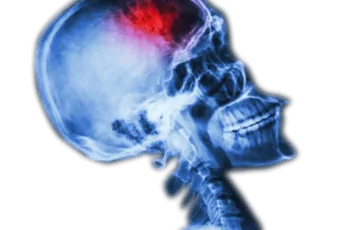

שבץ מוחי

שבץ מוחי, אירוע מוחי - המדריך עם כל המידע הרפואי והמעודכן שבץ מוחי או אירוע מוחי (Stroke) הוא הגורם הנפוץ ביותר לנכות בקרב בני הגיל השלישי וגורם התמותה השלישי בשכיחותו בעולם המערבי. בישראל מתים בכל שנה כ-15,000 איש, כתוצאה משבץ מוחי